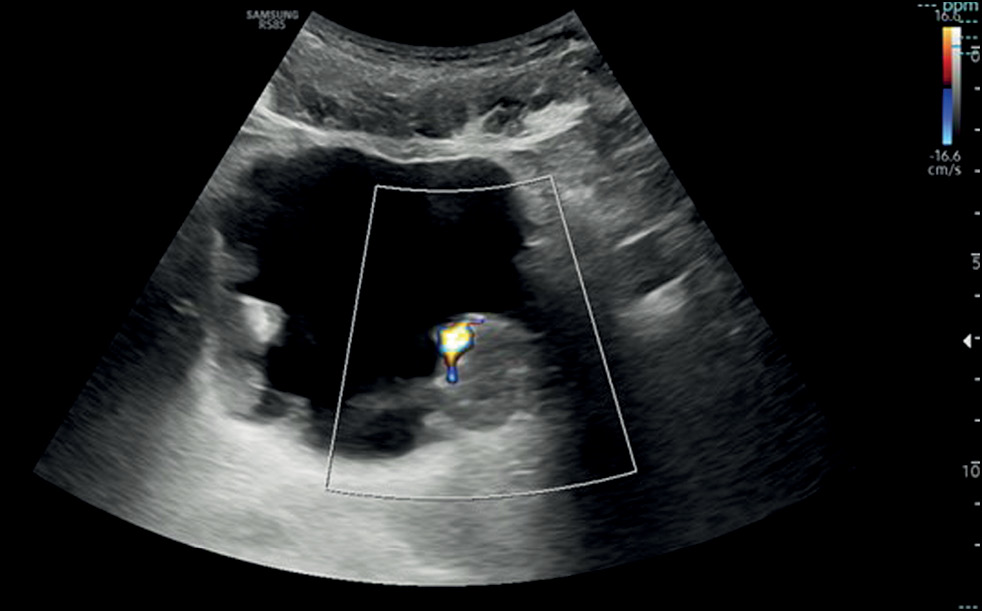

Role of artificial intelligence and novel visualization techniques in the early diagnosis of pancreatic cancer: a review

Abstract

Pancreatic ductal adenocarcinoma is the most common pancreatic cancer. It is characterized by a progressive course or distant metastases in 80%–85% of cases. Despite advances in understanding of pancreatic ductal adenocarcinoma, the disease is consistently linked to poor prognosis due to late diagnosis and limited treatment options in advanced stages. Recently, image processing using artificial intelligence has been introduced for pancreatic ductal adenocarcinoma diagnosis and demonstrated promising results. This review summarizes current scientific data, evaluates the role of artificial intelligence in imaging and early detection of pancreatic ductal adenocarcinoma, and identifies issues that warrant further investigation. The search for publications was conducted using PubMed, Google Scholar, and eLibrary. The following Russian and English search keywords were used: ранняя диагностика рака поджелудочной железы (early diagnosis of pancreatic cancer), искусственный интеллект (artificial intelligence), протоковая аденокарцинома поджелудочной железы (pancreatic ductal adenocarcinoma), медицинская визуализация (medical visualization), наночастицы (nanoparticles), pancreatic cancer, artificial intelligence, early diagnosis pancreatic ductal adenocarcinoma, and pancreatic cancer imaging. Significant progress in early detection of pancreatic ductal adenocarcinoma using artificial intelligence technologies was observed. Current approaches include pre-imaging risk stratification and increased data volume by analyzing electronic medical records. Despite substantial achievements, the clinical implementation of artificial intelligence technologies remains challenging. The use of artificial intelligence along with biomarkers is a promising direction and may enhance theranostics of various malignancies, including pancreatic ductal adenocarcinoma.